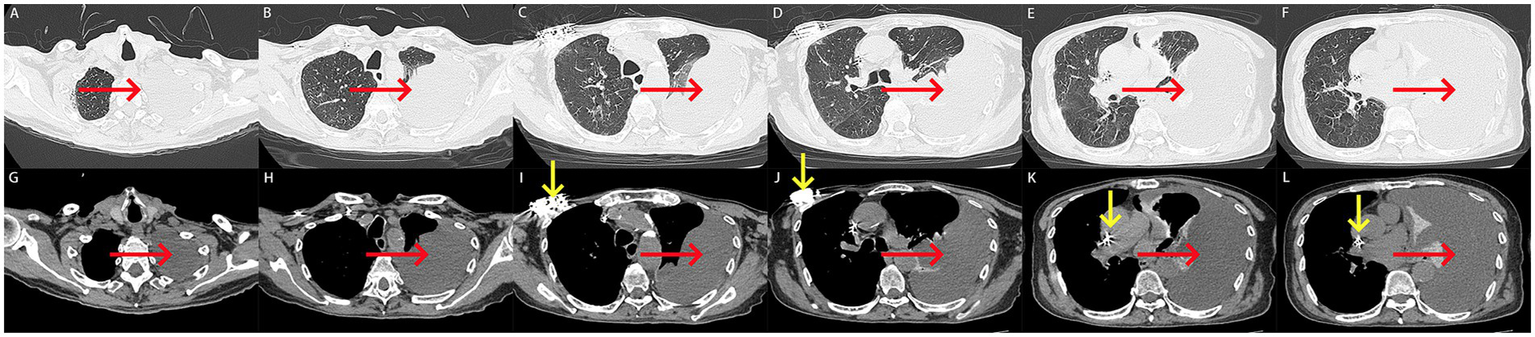

Computed tomography (CT) performed on August 5, 2024, revealed a large left-sided pleural effusion with adjacent pulmonary atelectasis and the presence of a cardiac pacemaker (Figures 2A–L).

Figure 2

(A–L) Computed tomography scan on admission. (A–L) A large left-sided pleural effusion with adjacent pulmonary atelectasis was revealed on computed tomography (red arrow). A cardiac pacemaker was seen on computed tomography (yellow arrow).